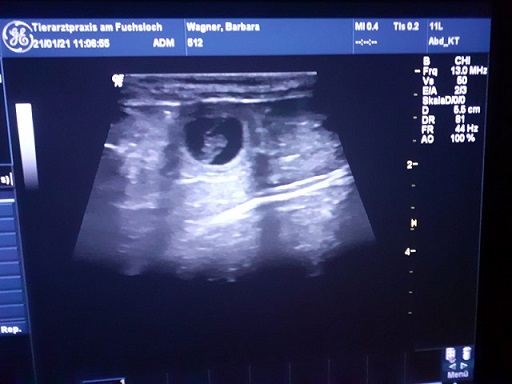

Wir waren am 21.01.2021 beim Ultraschall

Vicky ist schwanger

leider ist die Aufnahme diesmal nicht sehr gut gelungen

von meinem Tierarzt,

er konnte mir nicht sagen wie viele es werden